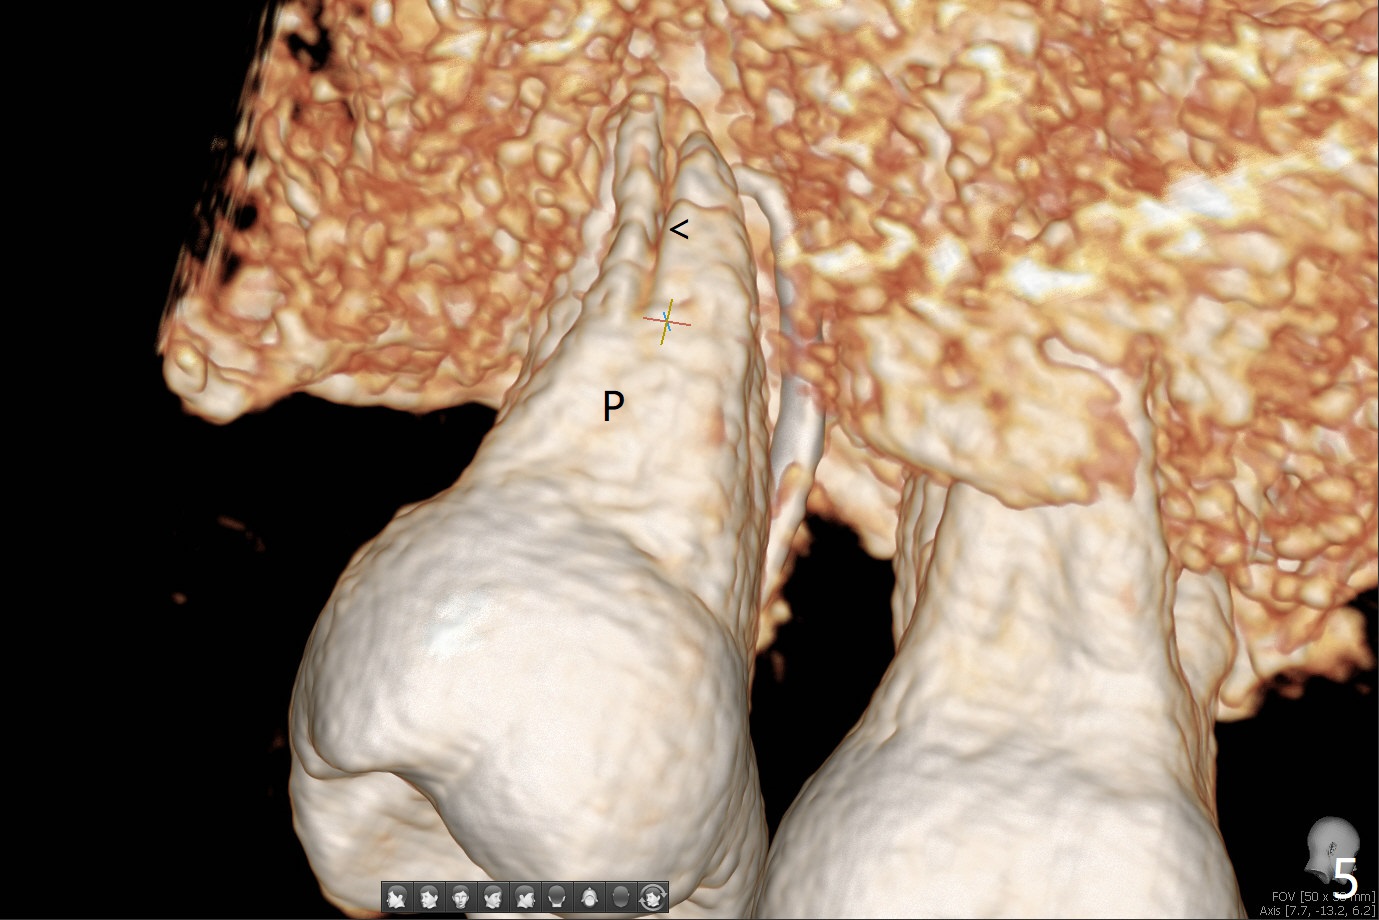

术后二周牙周敷料松动,取出后,伤口尚可(图三)。可能病人用右侧咀嚼,造成右上两个双尖牙松动疼痛,拔出后即刻种植修复,之后她能在右侧咀嚼,而食物撞击左上拔牙创疼痛,无法吃饭。术后三个月左上7疼痛,瘘道,插入牙胶尖(图四:*),根周阴影。其实腭侧根纵裂(图四,五:<),三个月已经发生(图二),可以即刻种植(图六),与5延期种植同时进行,使用导板。